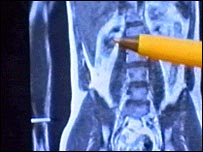

डायबिटीज़, दिल और गुर्दे की बीमारी के अलावा कई ख़तरनाक बीमारी मोटापे और शरीर में बढ़ती चर्बी के कारण होती है. लेकिन अब वैज्ञानिकों का कहना है कि स्कैन से शरीर के अहम अंदरुनी अंगों के आसपास जमा चर्बी यानी फ़ैट का पता लगाया जा सकता है. पश्चिमी लंदन का हैमरस्मिथ अस्पताल यूरोप का एकमात्र अस्पताल है जहाँ इस 'एमआरआई स्कैन' या 'फ़ैट स्कैन' की सुविधा मौजूद है. वैज्ञानिक कहते हैं कि 40 प्रतिशत लोगों के हृदय या गुर्दे के आसपास नुक़सानदेह चर्बी जमा रहती है हालाँकि इनमें से ज़्यादातर दुबले-पतले दिखते हैं. वैज्ञानिकों ने चेतावनी दी है कि दुबले-पतले होने के बावजूद भी इस चर्बी की वजह से डायबिटीज़ जैसी बीमारी की संभावना बन सकती है. प्रमाण प्रमाण सुझाते हैं कि मोटापे से ज़्यादा इस बात का सेहत पर असर होता है कि अवांछित चर्बी शरीर में किस जगह पर मौजूद है. उदाहरण के तौर पर हृदय रोग और टाइप 2 डायबिटीज़ का ख़तरा उन लोगों को ज़्यादा रहता है जिनके शरीर के मध्य भाग में ज़्यादा वज़न होता है. हालाँकि डॉक्टर बॉडी मास इंडेक्स (बीएमआई) की मदद से इस बात का अंदाज़ा आसानी से लगा सकते हैं कि किसी व्यक्ति का मोटापा उसकी लंबाई के हिसाब से ठीक है या नहीं. लेकिन छिपी हुई नुक़सानदेह चर्बी का पता लगाना आसान नहीं है. स्वास्थ्य शोध संस्थान के वैज्ञानिक और इस शोध के प्रमुख प्रोफेसर जिमी बेल ने बताया, "बीएमआई तकनीक से इस बात का सही-सही अंदाज़ा नहीं लग पाता कि शरीर में कितनी चर्बी मौजूद है." प्रोफेसर बेल ने कहा, "महत्वपूर्ण ये है कि चर्बी शरीर के किस हिस्से में मौजूद है. आमतौर पर फ़ैट अच्छा होता है लेकिन जब इसकी मात्रा ज़्यादा हो या फिर ये शरीर में ग़लत जगह पर मौजूद हो तो ये नुक़सानदेह होता है ”. अंदरुनी चर्बी की मात्रा एमआरआई स्कैन से ये पता लगाया जाता है कि शरीर के अंदरुनी अंगों के आसपास ख़तरनाक फ़ैट मौजूद तो नहीं है. प्रोफेसर बेल के मुताबिक़ जब डॉक्टरों को इस बात का पता चल जाता है कि व्यक्ति के शरीर में छिपे हुए फ़ैट की मात्रा ज़्यादा है तो वे व्यायाम और स्वास्थ्यवर्धक खान-पान से इसे हटाने के प्रयास कर सकते हैं. उन्होंने बताया, "हम उन कारणों का पता लगाने की कोशिश कर रहे हैं जिनकी वजह से लोगों के शरीर के अंदरुनी अंगों के आसपास चर्बी जमा हो जाती है ”. डॉक्टर बेल ने बताया कि इसके बाद ये पता लगाया जाएगा कि इस चर्बी को हटाने के लिए लोगों को क्या करना चाहिए. प्रोफ़ेसर बेल का मानना है कि कम खाना खाने से नुक़सानदेह चर्बी से छुटकारा नहीं मिलता, इसकी बजाय व्यायाम से लाभ मिलता है. | इससे जुड़ी ख़बरें मोटापा पहुँचा सकता है पैरों को नुक़सान26 नवंबर, 2006 | विज्ञान डायबिटीज़ के बढ़ते ख़तरे पर चेतावनी13 नवंबर, 2006 | विज्ञान मोटे लोगों के लिए ख़ास डिज़ाइनर कपड़े02 सितंबर, 2006 | भारत और पड़ोस मोटापा घटाने के लिए मंत्री नियुक्त23 अगस्त, 2006 | पहला पन्ना 'मोटापा रोकने के लिए बनी वैक्सीन'01 अगस्त, 2006 | विज्ञान टीवी और कंप्यूटर की 'लत' ख़तरनाक02 जून, 2006 | विज्ञान | |||||||||||||||||||||||||||||||||||||||||||||||||||||||||||||||||||||||||||||||||||||||||||||